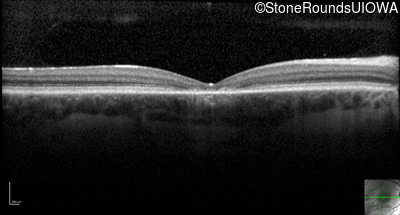

Optical Coherence Tomography - Left - 20/200

Exemplar / OCT Stack